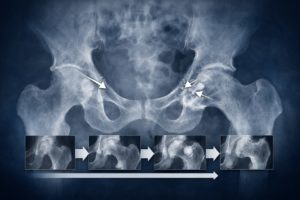

軽度の場合は、筋肉の繊維がごく一部だけ傷ついている状態とされ、歩行ができるケースも少なくないようです。一方で中度以上になると、部分的な断裂が起きている可能性があり、動作時の痛みが強くなる傾向があると紹介されています。